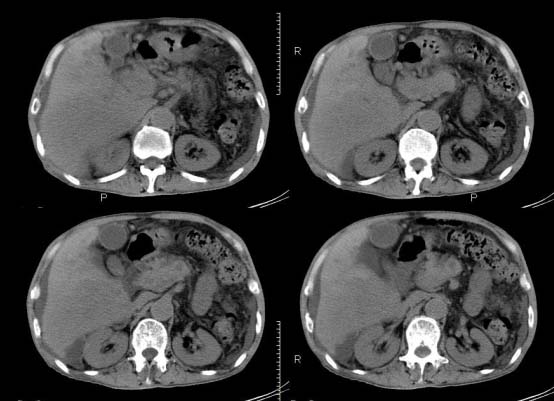

以下是引用杀毒软件在2010-3-30 18:11:00的发言:[br]考虑---hcc侵犯侵犯周围组织〔胰腺、胆管、肠系膜上动静脉〕伴门脉、下腔静脉癌栓形成、动-静脉瘘、肝门、腹腔动脉周围淋巴结转移可能性大、腹水。

以下是引用pujunzhi在2010-3-31 8:45:00的发言:[br]支持 肝癌并多发肝内转移,胰头、肝门、腹腔动脉周围淋巴结转移,下腔静脉癌栓形成,肝硬化、腹水。

以下是引用jsgdoctor在2010-3-30 20:42:00的发言:[br]考虑---hcc侵犯侵犯周围组织〔胰腺、胆管、肠系膜上动静脉〕伴门脉、下腔静脉癌栓形成、动-静脉瘘、肝门、腹腔动脉周围淋巴结转移可能性大、腹水。